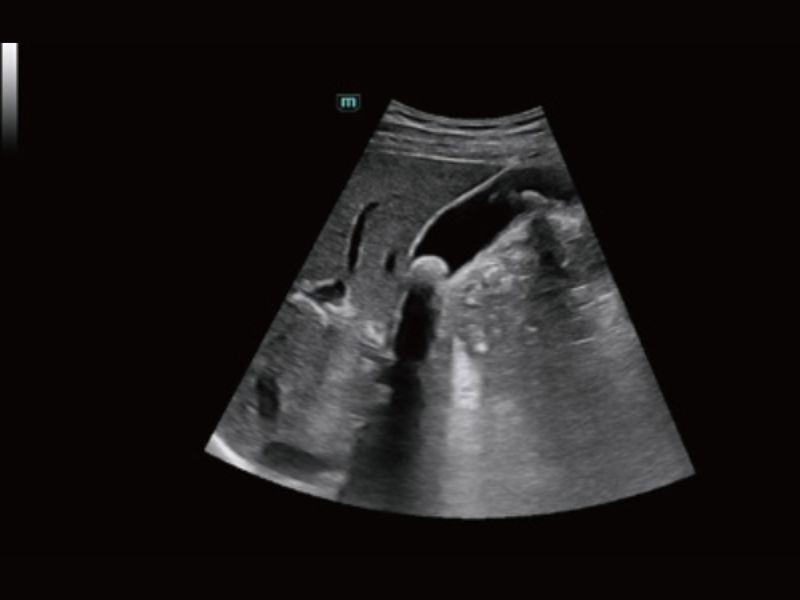

Cena Inteligente 3D

Solução obstétrica inteligente full-stack com tecnologia ZST⁺

Medição automática de biometria fetal